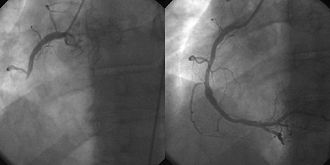

| Scan von 2 Videoprints einer selbst durchgeführten Prozedur | Übertragen aus de.wikipedia nach Commons. | JHeuser in der Wikipedia auf Deutsch | Datei:HWI PTCA.jpg | |